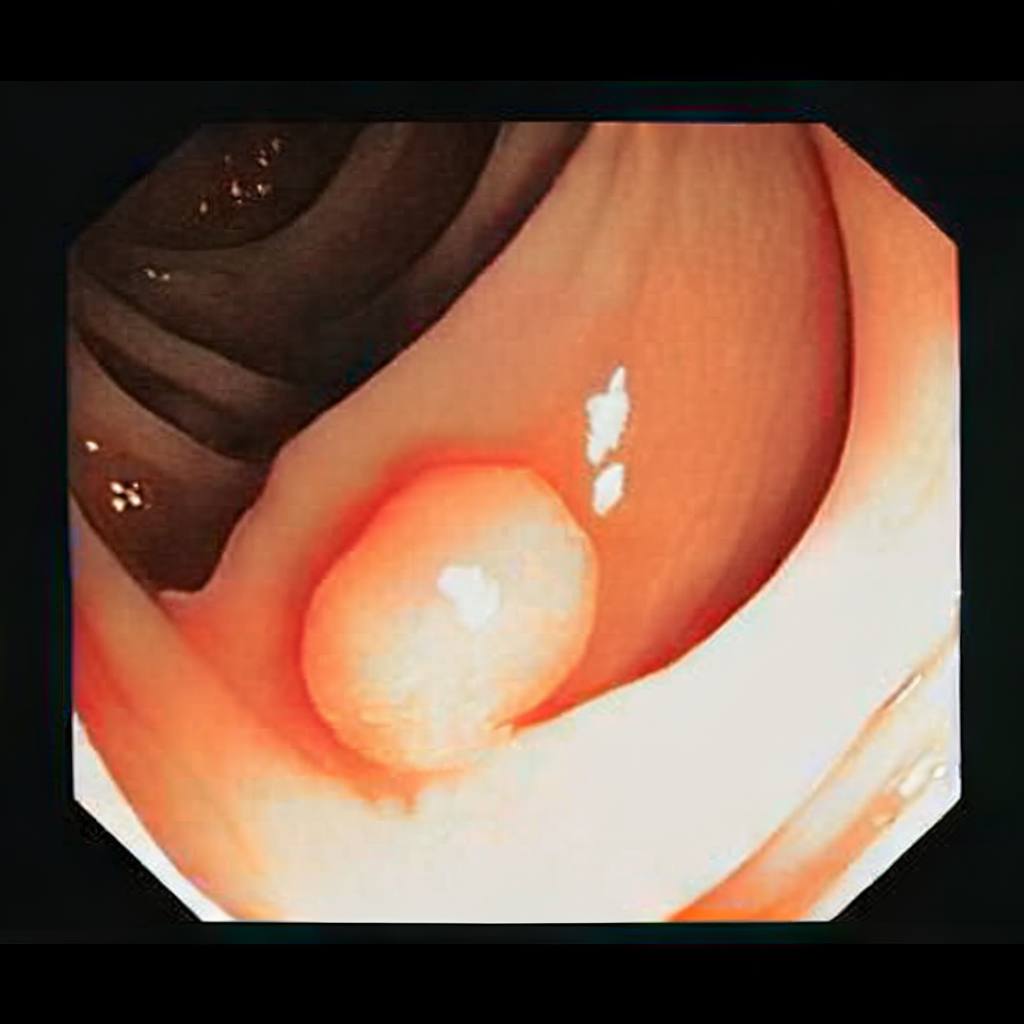

Diffusion models have recently gained significant traction due to their ability to generate high-fidelity and diverse images and videos conditioned on text prompts. In medicine, this application promises to address the critical challenge of data scarcity, a consequence of barriers in data sharing, stringent patient privacy regulations, and disparities in patient population and demographics. By generating realistic and varying medical 2D and 3D images, these models offer a rich, privacy-respecting resource for algorithmic training and research. To this end, we introduce MediSyn, a pair of instruction-tuned text-guided latent diffusion models with the ability to generate high-fidelity and diverse medical 2D and 3D images across specialties and modalities. Through established metrics, we show significant improvement in broad medical image and video synthesis guided by text prompts.

In this work, we focus on the ability of LDMs to generate novel datasets to overcome class imbalances traditionally associated with medical data, and potentially reduce the need for manual annotation of medical 2D and 3D data. We present MediSyn, a pair of text-guided latent diffusion models for broad medical 2D and 3D modality synthesis. To overcome the scarcity of labelled medical data, we leverage a vast corpus of more than 5 million image-caption pairs and 100,000 video-caption pairs collected from the public domain across numerous medical specialties, and integrate comprehensive natural language annotations to develop a pair of versatile diffusion models for the medical domain.

We collect and train on one of the largest publicly available datasets of medical images and videos to date, spanning more than 5 million image-caption pairs and 100,000 video-caption pairs (comprised of volumetric scans and image sequences) across 8 broad specialties and 9 image types.

Our findings demonstrate Medisyn’s remarkable ability to generate high-fidelity and diverse medical images, image sequences and volumetric scans across various medical subspecialties and imaging modalities. Other medical text-driven diffusion models, such as TauPETGen [42] for tau PET images and GenerateCT [43] for chest CT volumes, have proven successful in generating high-quality images that accurately depict anatomical features and clinical conditions. However, these models are constrained to a single imaging modality and anatomical region, thereby restricting their applicability. Moreover, they were trained on relatively small datasets sourced from a limited number of institutions, which could lead to more biased outputs. In contrast, Medisyn, having been trained on one of the largest publicly accessible medical image and video datasets to date, is equipped to synthesize data that cover numerous medical disciplines, population groups, and disease states. Leveraging our two models, we can synthesize new medical datasets as well as augment existing ones, potentially improving a wide array of medical machine learning tools, both general and specialized. Additionally, our models can minimize the need to repeatedly fine-tune on specific datasets for generating different imaging modalities, thus reducing computational costs for academic labs.